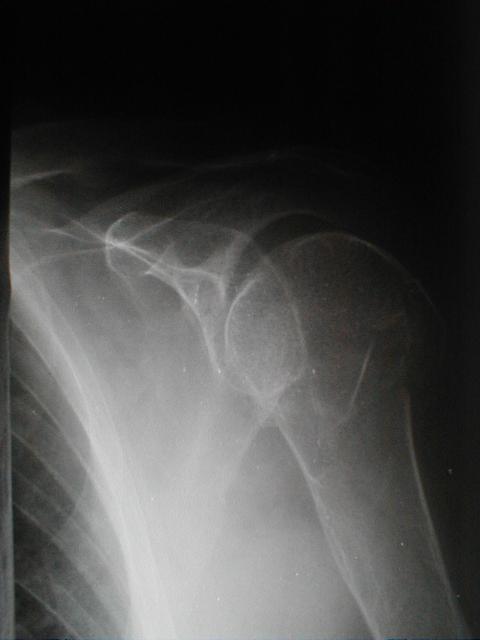

症例1

上腕骨頚部(外科)骨折と肩関節脱臼の合併症例

左上腕骨頚部(外転)骨折

左肩関節脱臼

経過

3日目]自発痛は消失したが起居動作は困難

[25日目] 起居動作は支障なくでき、自動運動を開始する

[35日目] 提肘を除去し日常生活動作をしやすくする。

[45日目] 自動運動で90°程度挙上可能となるが力が入らない

[50日目] 包帯除去し抵抗運動をさせる

[60日目] 日常生活になんら支障なく治癒とす